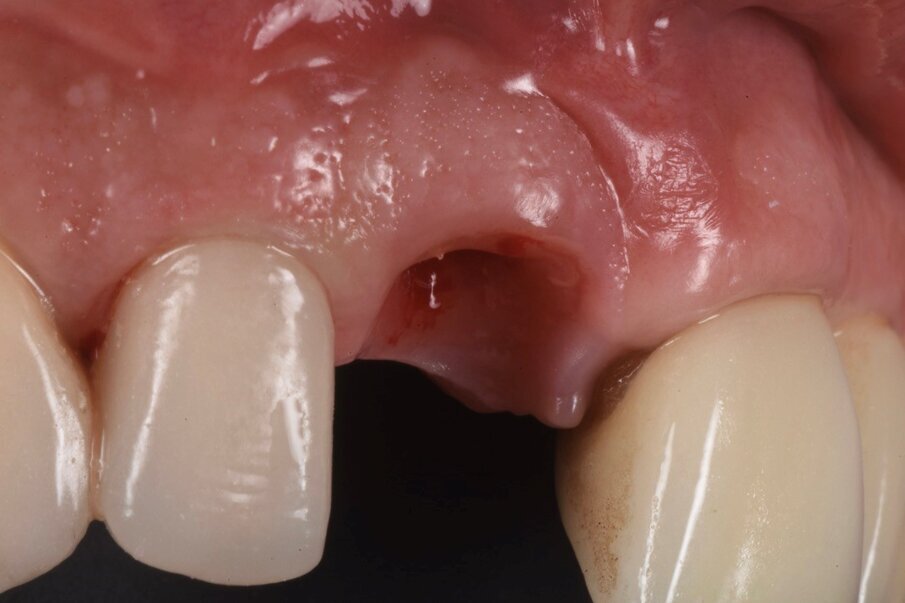

Le radiografie del caso completato nell’inizio del 2010 (Fig. 4) evidenziano la precisione del lavoro che è poi stato mantenuto nel corso degli anni. L’incisivo centrale destro 11 era stato trattato con apicectomia in passato ed era l’unico dente non vitale della riabilitazione. La paziente era seguita dal protesista che aveva portato a termine il caso. Nel 2021 la signora si è ripresentata con sintomatologia sul dente 21. Il lavoro eseguito nel 2010 era ancora in buone condizioni fatta eccezione per 11-12 ove 12 presentava una recessione gengivale con esposizione del collarino della cappetta galvanica che supportava la corona in ceramica e 11 presentava una piccola fistola nella sua porzione vestibolo distale (Figg. 5-7). La diagnosi era abbastanza semplice, l’11 aveva una frattura verticale e una prognosi infausta.

A questo punto veniva avvitato sull’impianto un moncone provvisorio, completato l’innesto di materiale biocompatibile con osso equino collagenato (OX granules, Bioteck) nel gap esistente tra la fixture e la lamina, poi veniva connessa al moncone provvisorio la corona provvisoria in resina (Fig. 13). La rx di controllo post intervento evidenzia la buona riuscita della procedura e la corretta connessione tra moncone e fixture (Fig. 14). Sei mesi più tardi alla rivalutazione e rimozione della corona provvisoria (Fig. 15) si può ben notare come questa procedura abbia permesso di mantenere integri i tessuti peri-implantari, di aver favorito la creazione di un tunnel mucoso spesso e maturo. I tessuti con e senza la corona provvisoria mostrano un aspetto naturale e le caratteristiche di una gengiva in salute (Figg. 16a, 16b).